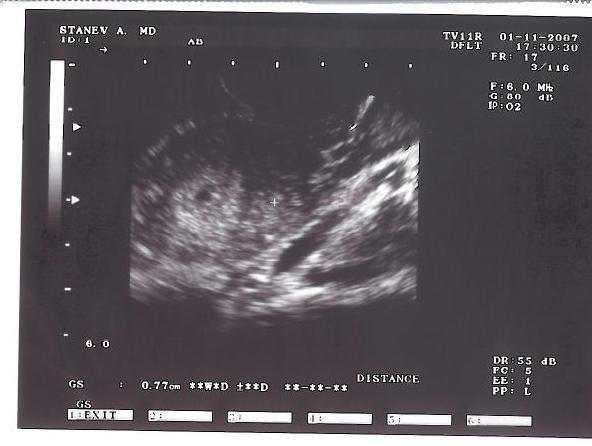

Ултразвука му е доста стар и несъвършен и можеби затова нищо не видя тоя път, но аз все пак съм притеснена, защото след 21вия ден се появява сърцето, а вчера ми беше 25тия. Ох, дано всичко да е наред